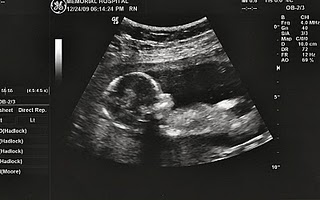

Half Way, baby

You are 20 weeks old today, Jan 20 2010. Our last appointment was 2 weeks ago. You got anatomy sonogram and we found out that you are a BOY!!!.

We are very happy that you are doing great. I had some tears in my eyes when I saw your movement and when the PA told me that you look like a healthy little boy. We have been waiting for you for so long and I can tell you; you are worth waiting for.